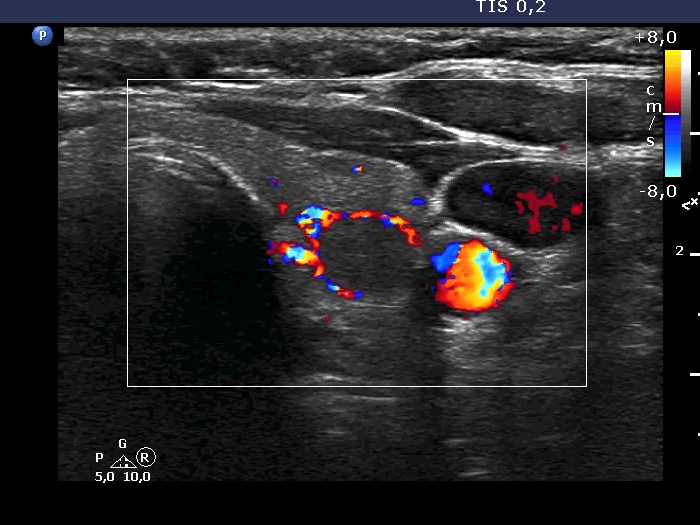

Left lobe, transverse scan, color Doppler mode. The nodule shows perinodular vascularity.